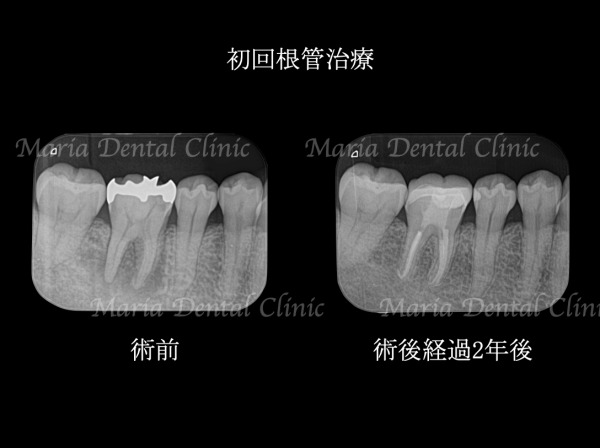

「精度」を高める先端医療機器の活用

将来的な健康につなげる確かな治療には、診査や治療の精度を高める先端医療機器の活用が欠かせません。当院ではマイクロスコープ(歯科用顕微鏡)や歯科用CTなどの先端設備を導入し「精度」を追求しています。

当院が大切にしているのは、できるだけ安心して治療を受けていただくこと、そして結果を実感していただくことです。そのために、院内の衛生管理体制やバリアフリー設計など環境面にもこだわり、患者様ができるだけ不安やストレスを感じないよう配慮。そして、マイクロスコープや歯科用CTなどの先端医療機器を活用し、精密根管治療を得意とする院長や大学病院から招いた歯科医師でチームを組んで、専門性の高い治療をご提供しています。